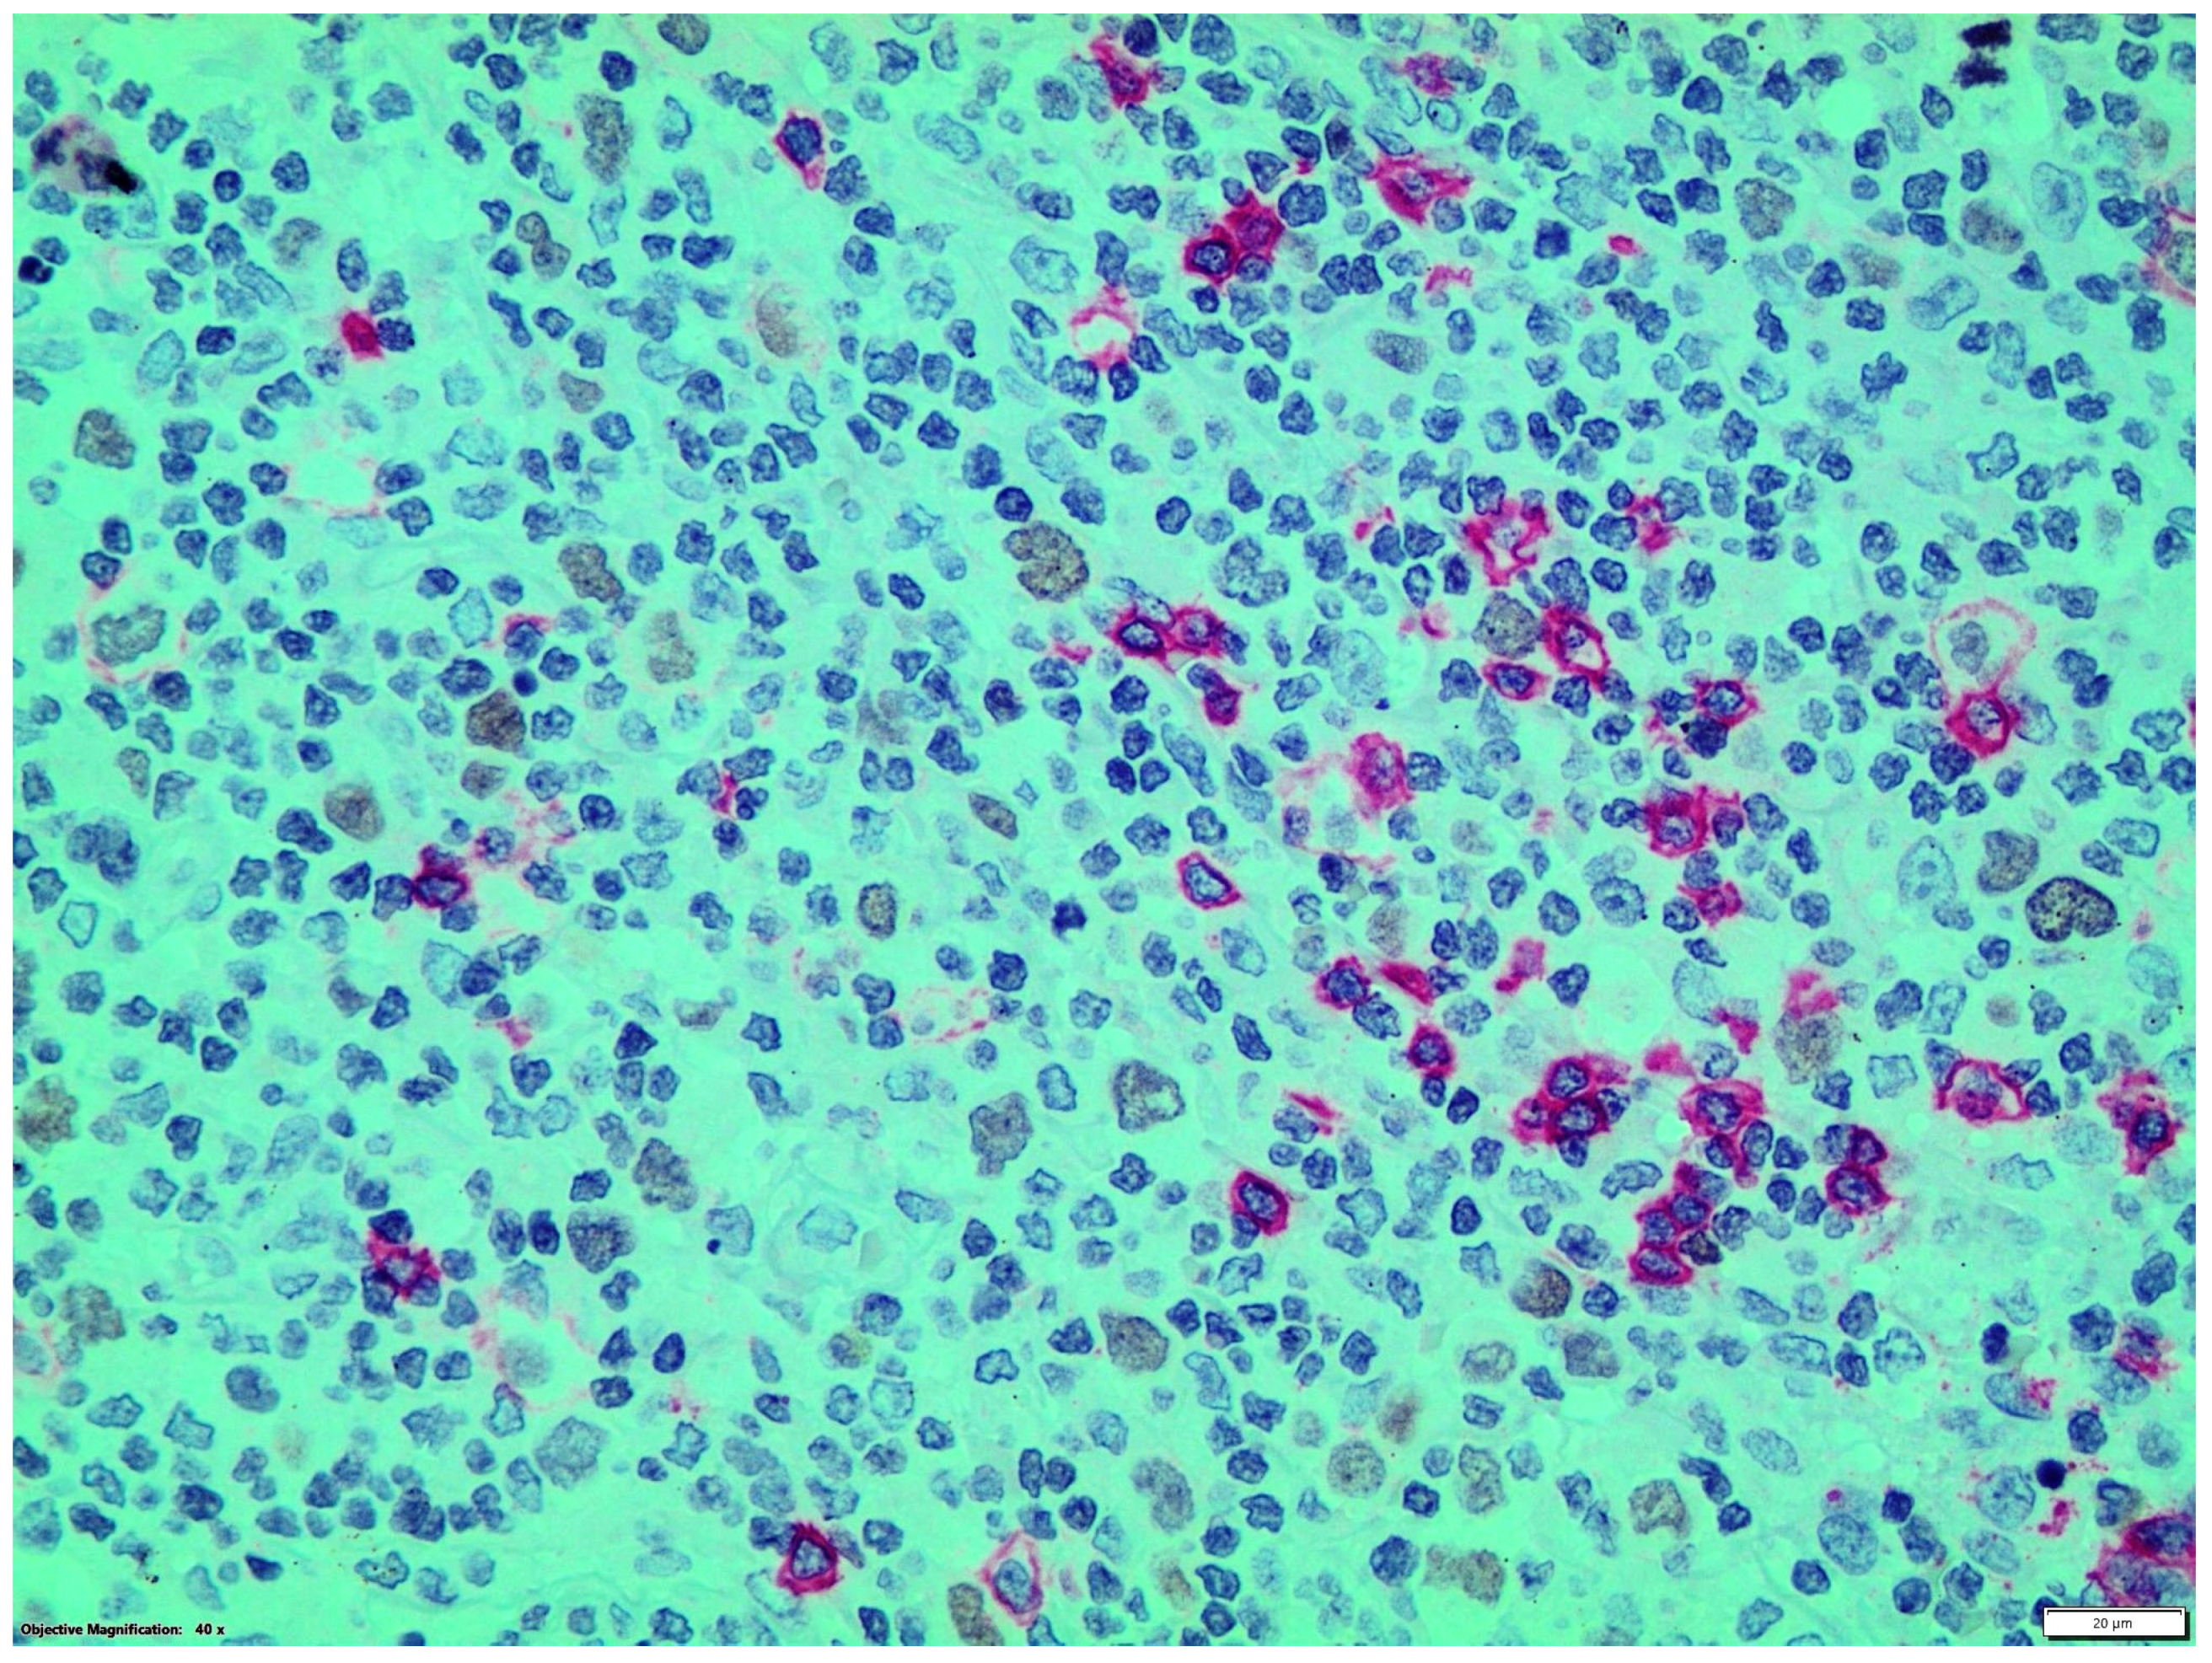

Double immunostainings showed that nuclear GATA3 was expressed by some CD30+ or CD15+ HRS cells and by a few CD3+ T-cells which were frequently organized as small groups, distant from HRS cells. GATA3 nuclear expression was not detected in CD20, CD56 or CD68 + cells (Figure 2 and Figure 3).

Figure 2.

Double streptavidin-biotin peroxidase-labeled (LSAB) (brown staining)/alkaline phosphatase/anti-alkaline phosphatase (APAAP) (red staining) immunohistochemical procedure: CD20+ (red staining)/GATA3- B-cells and CD20-/GATA3+ (brown staining) HRS cells (magnification ×400).